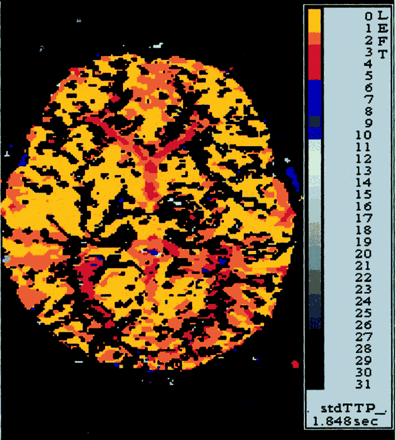

病人气管切开后的第二天点燃,能够将第二天左胳膊和腿。一周后,这个孩子被动态。点燃了两周后,病人没有残疾在日常生活活动或休闲活动。她经历了一个最小的干扰,同时保持一个较高的位置左胳膊。考试成绩的运动强度(手测功器)和finger-hand协调(手指敲击,将挂钩孔)是在正常范围内。神经心理学评估显示没有语言障碍的迹象,认知或行为。MRI显示一个小纹状体梗死保留内囊(图1 b)。时间进程和振幅的电位诱发外展digiti最小的经颅磁刺激肌肉的皮质是在正常范围内,表示对称完整锥体束功能(延时的左臂,13.8毫秒;延迟的右臂,11.2毫秒)。灌注加权核磁共振没能证明正确的MCA血流动力学妥协领土(图3)。